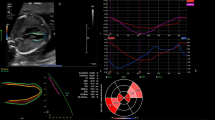

Strengths and Limitations

The strength of this study, we believe, is the simplicity in which ventricular measurements derived from speckle tracking analysis can be generated from a single 4-chamber view in less than 5 min. The measurements in Table 10, used to compute the probability for requiring neonatal BAS, can be obtained using the length, width, and area measurements available on all fetal ultrasound machines. Supplement 2 is an Excel spreadsheet (Fig. 3) that provides a calculator with images describing the measurements to compute the probability of requiring urgent neonatal BAS. Limitations of the study include its retrospective nature and that not all fetuses were evaluated in the 3rd trimester when the pathophysiology of the abnormal measurements should be most obvious. Prospective evaluation of fetuses with D-TGA will be beneficial to test the Excel calculator developed from these study results.

Calculator to compute the probability of requiring a neonatal urgent BAS. To use the calculator the user enters the gestational age and measurements illustrated below the calculator. Once entered the z-scores and probability are calculated. The clear the calculator of the measurements and computed values, the user clicks the blue button “Reset Calculator.” RV right ventricle, LV left ventricle, LA left atrium, RA right atrium